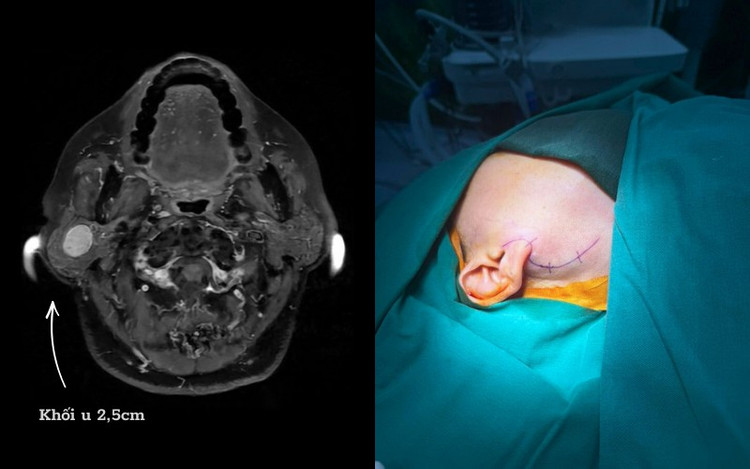

Trường hợp bệnh nhân D. là ví dụ điển hình, người bệnh phát hiện khối u tuyến mang tai phải từ nhiều năm trước, có biểu hiện sưng lệch vùng góc hàm, thỉnh thoảng đau tức. Dù đã được chỉ định phẫu thuật từ sớm nhưng bệnh nhân liên tục trì hoãn do lo ngại có nguy cơ liệt mặt sau mổ.

U tuyến nước bọt mang tai của chị D có vị trí phức tạp - Ảnh BVCC

Tiếp nhận thăm khám cho bệnh nhân D., ThS.BSNT Nguyễn Xuân Quang - Trưởng khoa Tai mũi họng và Phẫu thuật Đầu Cổ, Bệnh viện Đa khoa Hồng Ngọc cho biết, việc người bệnh trì hoãn điều trị trong thời gian dài khiến khối u tiếp tục phát triển, làm tăng nguy cơ chèn ép và tổn thương dây thần kinh mặt, điều này sẽ khiến ca mổ trở nên phức tạp hơn.

Ca phẫu thuật của bệnh nhân D. kéo dài khoảng 3 giờ, kết quả thành công tốt đẹp. Khối u được lấy trọn vẹn mà không cần cắt bỏ toàn bộ tuyến mang tai. Sau mổ, người bệnh D. hồi phục tốt, không ghi nhận liệt dây thần kinh mặt.

Đặc biệt, gương mặt cân đối, không méo lệch, chức năng vận động và yếu tố thẩm mỹ được bảo tồn nguyên vẹn.